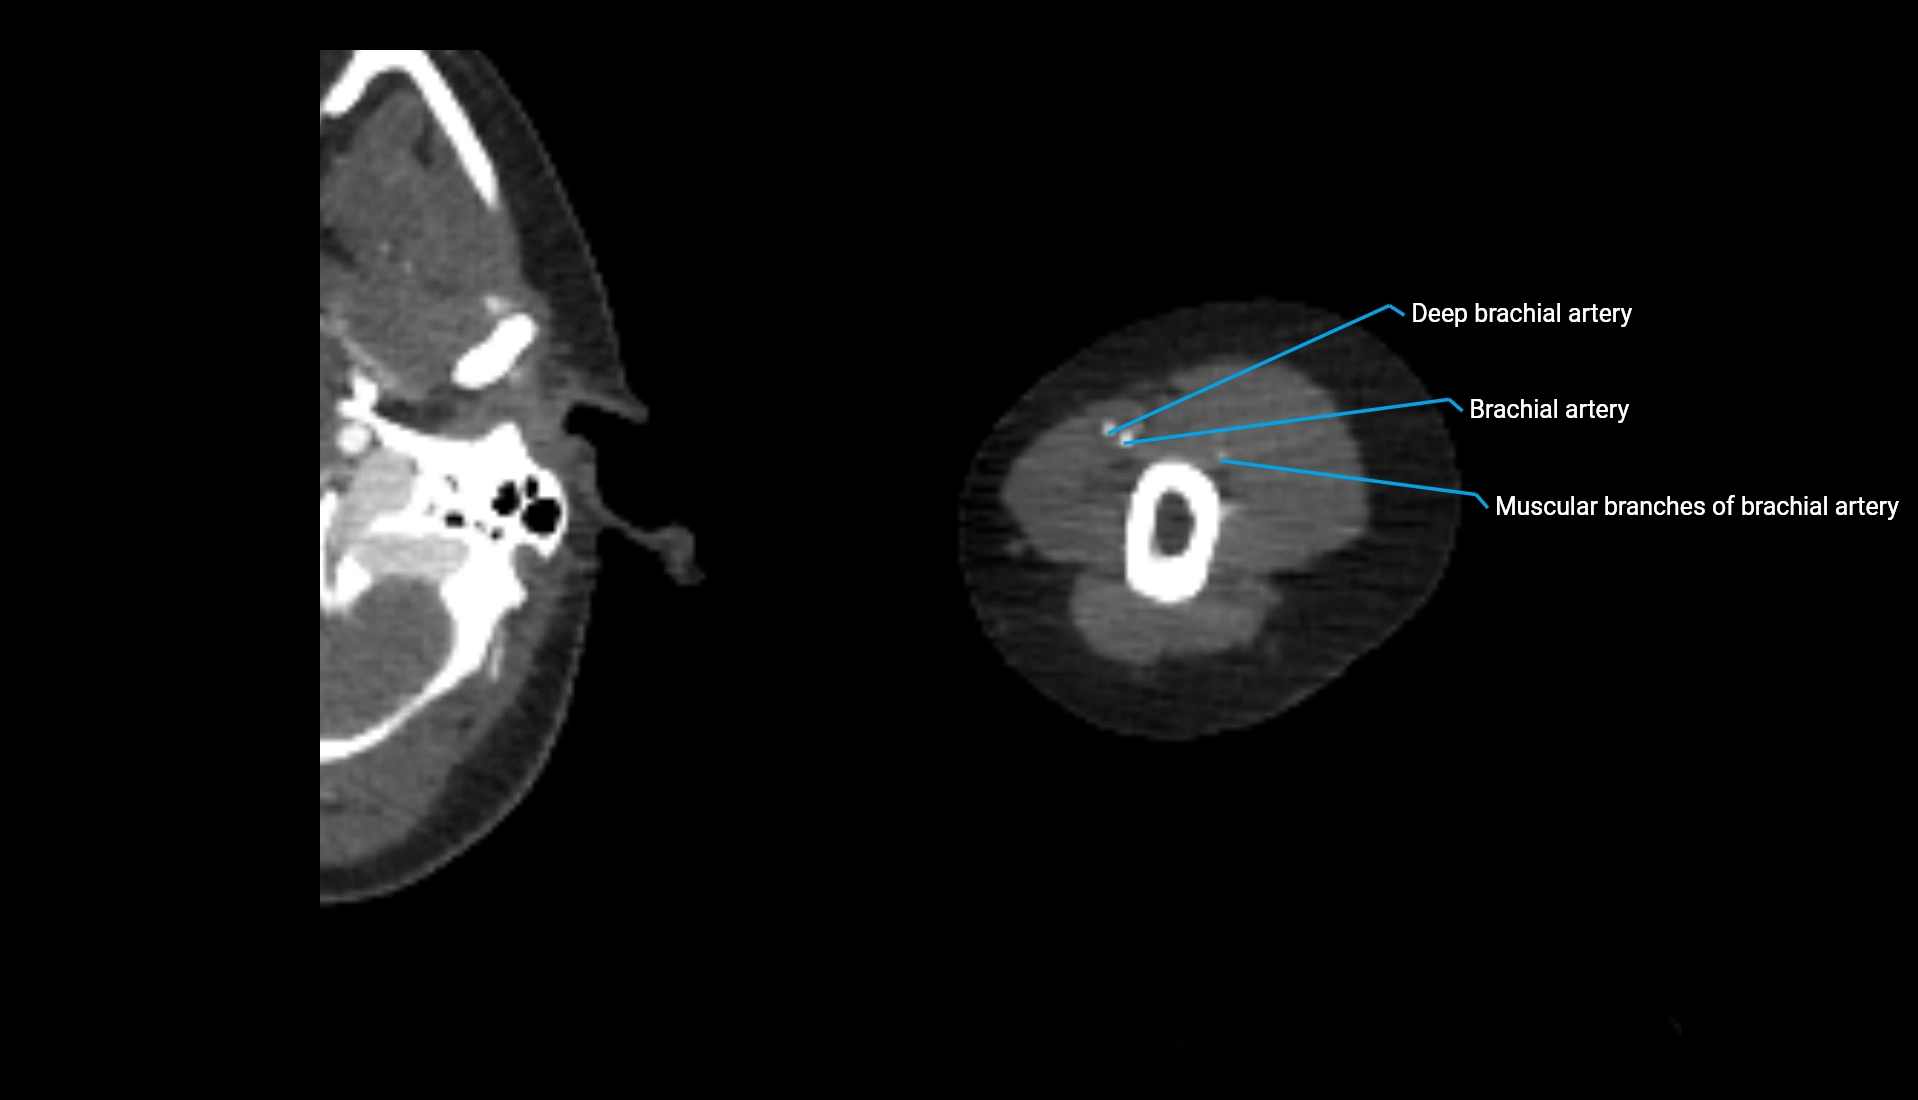

CT Appearance

Non-Contrast CT:

• Cortex: High-density, sharply defined

• Subchondral bone: Dense cancellous matrix

• Articular surface: Smooth concave contour articulating with the capitellum

• Excellent for evaluating bone integrity, alignment, and subtle fractures

Post-Contrast CT:

• Bone: No enhancement

• Joint capsule and synovium: Mild enhancement outlining the joint

• Improves contrast between soft tissues and bony margins

• Useful in detecting subtle joint abnormalities or postoperative changes